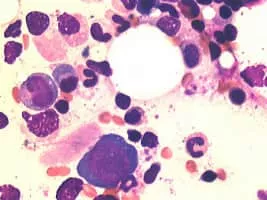

Parvovirus photograph

Parvovirus

Parvovirus is the common name applied to all the viruses in the Parvoviridae taxonomic family, although it can also be used specifically for members of one of the two Parvoviridae subfamilies, the Parvovirinae, which infect vertebrate hosts.